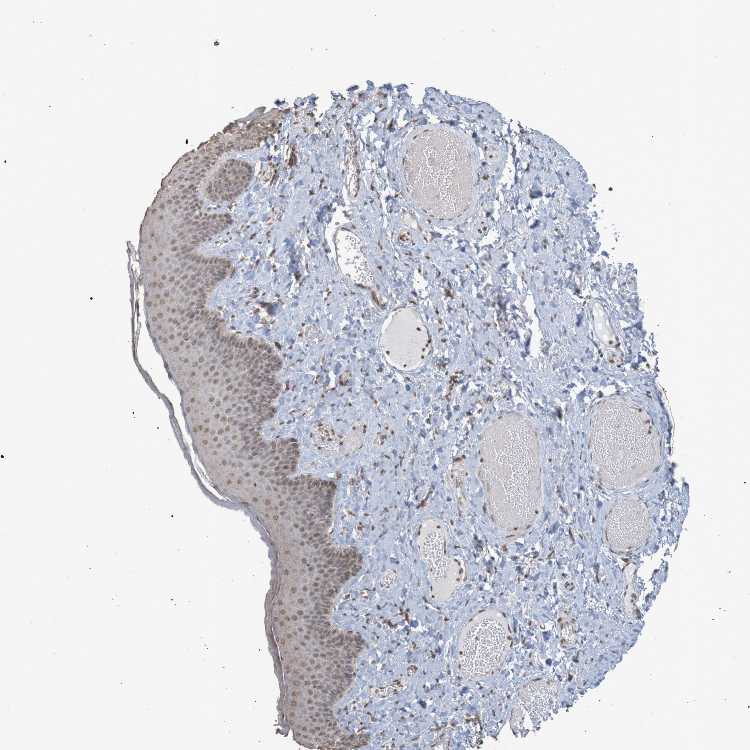

SKIN 2 - Antibody stainingi

Antibody staining in the annotated cell types in the current human tissue is reported as not detected, low, medium, or high, based on conventional immunohistochemistry profiling in selected tissues. This score is based on the combination of the staining intensity and fraction of stained cells.

Each image is clickable and will lead to virtual microscopy that enables deeper exploration of all samples and also displays staining intensity scores, fraction scores and subcellular localization as well as patient and tissue information for each sample.

Antibody CAB011197

Epidermal cells Medium